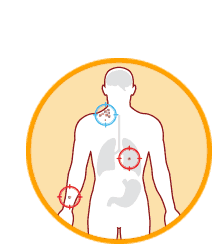

Cancer is identified in the body.

Educated immune cells identify and attack tumors throughout the body.